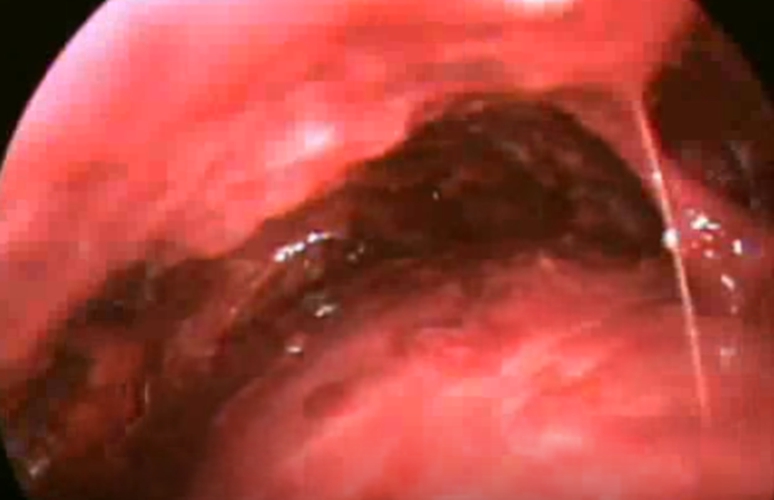

結核性胸膜炎胸腔鏡

結核性胸膜炎引流

結核性胸膜炎胸腔鏡的